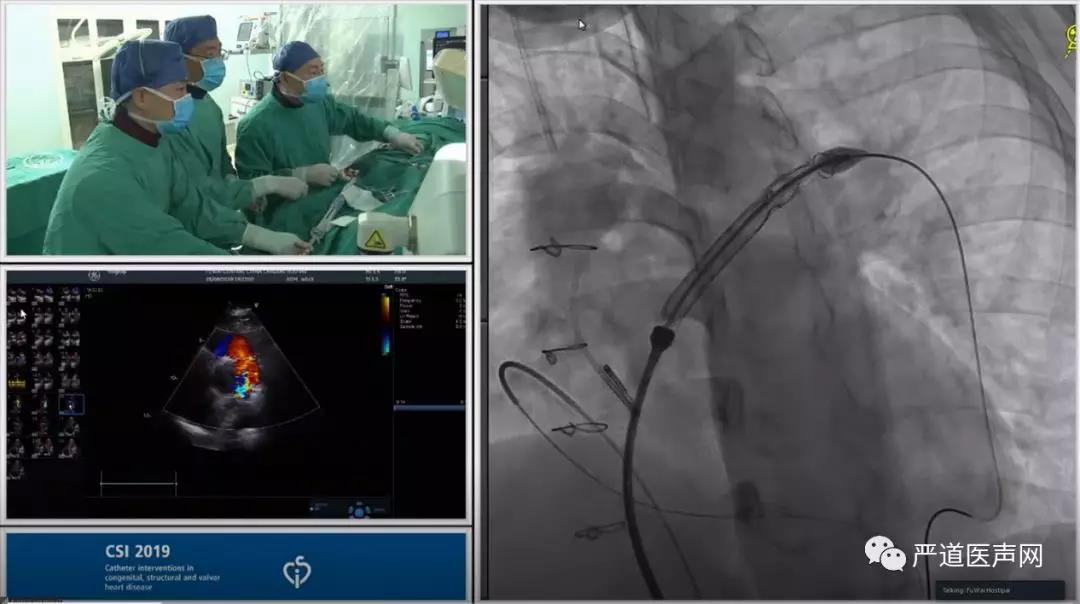

张戈军教授团队手术同步网络直播

• 造影结果

肺动脉造影显示患者肺动脉主干增宽,左右肺动脉未见明显狭窄,肺动脉瓣大量返流。随后注入肝素5000U,选择AGA公司34mm球囊测量直径的同时行主动脉根部造影,结果提示患者冠脉显影良好,未受到压迫。

右股静脉交换加硬导丝,置换24FGore血管鞘,送入输送鞘管及30*25mm VENUS P带瓣支架,反复造影定位后释放瓣膜。再次造影确定瓣膜位置良好,冠脉显影良好,床旁超声检查显示支架瓣膜启闭正常,未见明显返流及瓣周漏,跨瓣压差仅6mmHg。